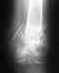

описание рентгенолога:Перелом внутренней лодыжки без смещения, сложный перелом и/з диад** м/берцовой кости, со смещением, отрыв основания б/берцовой кости без смещения. 29.10.13 была проведена операция остеосинтеза правого голеностопа, сделан снимок наложена лангета и я отправлен домой на 1 месяц. Вопрос правильно ли проведена операция и когда я смогу самостоятельно ходить без костылей и не стану ли я инвалидом?